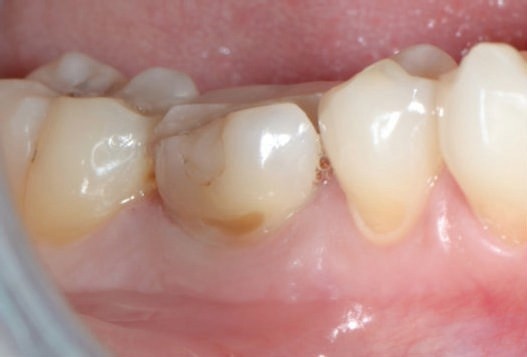

- Причинами удаления зубов были неудачи эндодонтического лечения, прогрессирующий кариес и разрушения (рис.1 и 2);

Рис.1в. Нереставрируемый первый большой кореной зуб нижней челюсти. (a) Исходная клиническая картина; (б) периапикальная рентгенограмма; (в) окклюзионный вид, показывающий мезиодистальное разрушение.